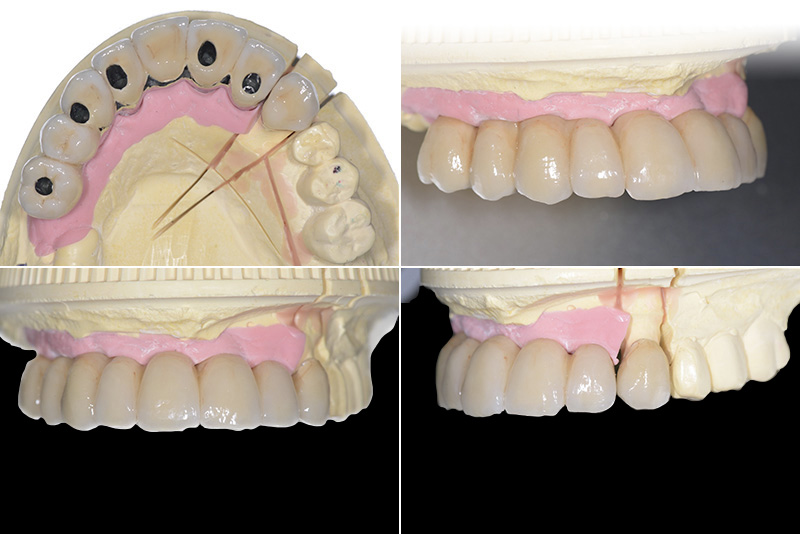

PREMESSA: in seguito all’estrazione dell’incisivo laterale superiore di destra, resasi necessaria per cause batteriche, si decide di affrontare il caso con il posizionamento di un impianto in sostituzione dell’elemento mancante dopo guarigione del sito infetto. Con tecniche rigenerative sia dei tessuti ossei mancanti a causa dell’infezione pregressa, sia dei tessuti gengivali che appaiono inizialmente troppo spostati in alto, si ripristina una corretta morfologia delle parabole (contorni) gengivali e delle papille interdentali (triangoli di gengiva tra due denti vicini).

Vengono utilizzati 2 tipi di provvisori: il primo, cementato ai denti vicini, viene utilizzato dal momento dell’estrazione del dente fino ad impianto osteointegrato (circa 6 mesi); il secondo, avvitato direttamente all’impianto, ha una funzione di prova estetica ma soprattutto di guida per la maturazione dei tessuti gengivali peri-implantari portandoli verso la maturazione completa prima di posizionare la corona finale in disilicato di litio.